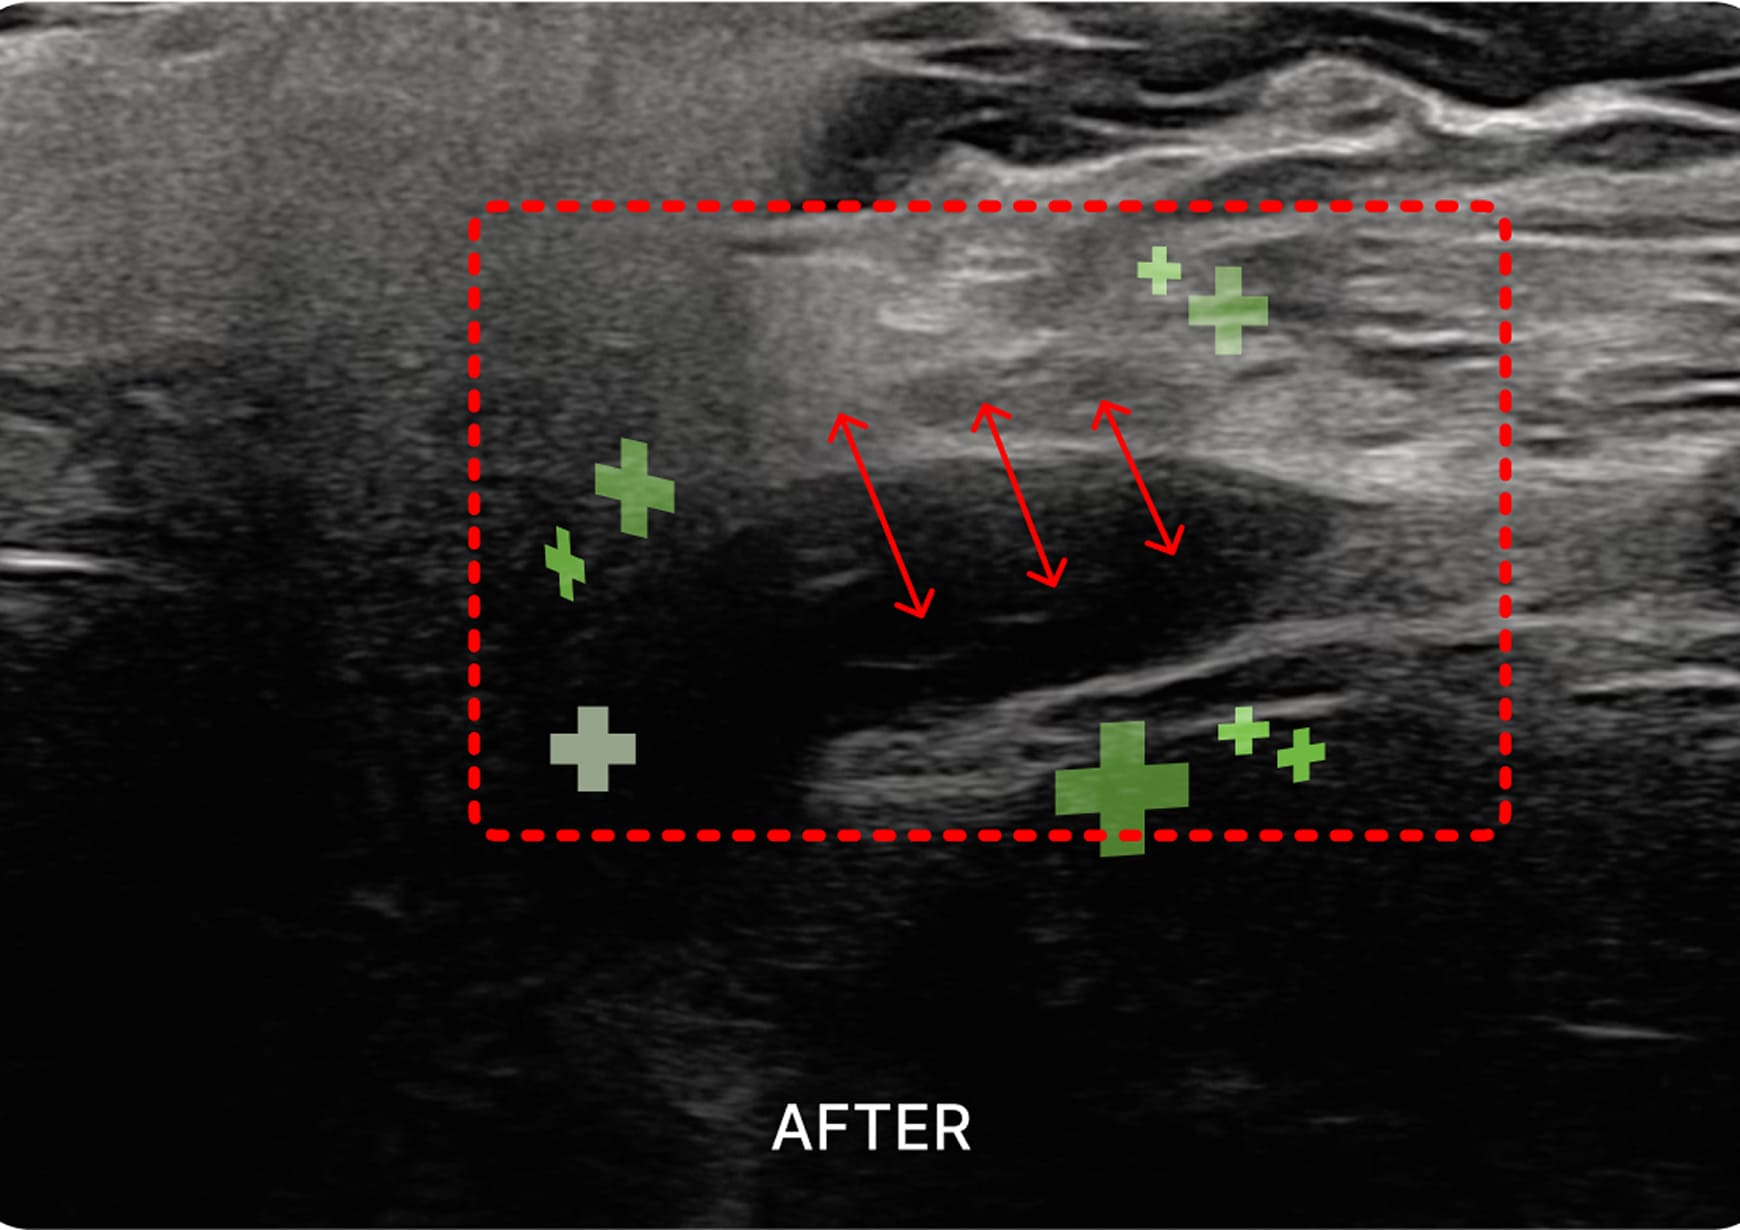

초음파 검사

1. 초음파 시술

초음파를 활용하여 근육과 신경 문제를

정확히 진단하고 치료하여 통증과 기능

이상을 개선하는 시술입니다.

경신경총 / 경장근

두면부 및 상지의 긴장성 근육 문제를 해결하여

두통, 어지럼증, 상지 저림 등을 완화합니다.